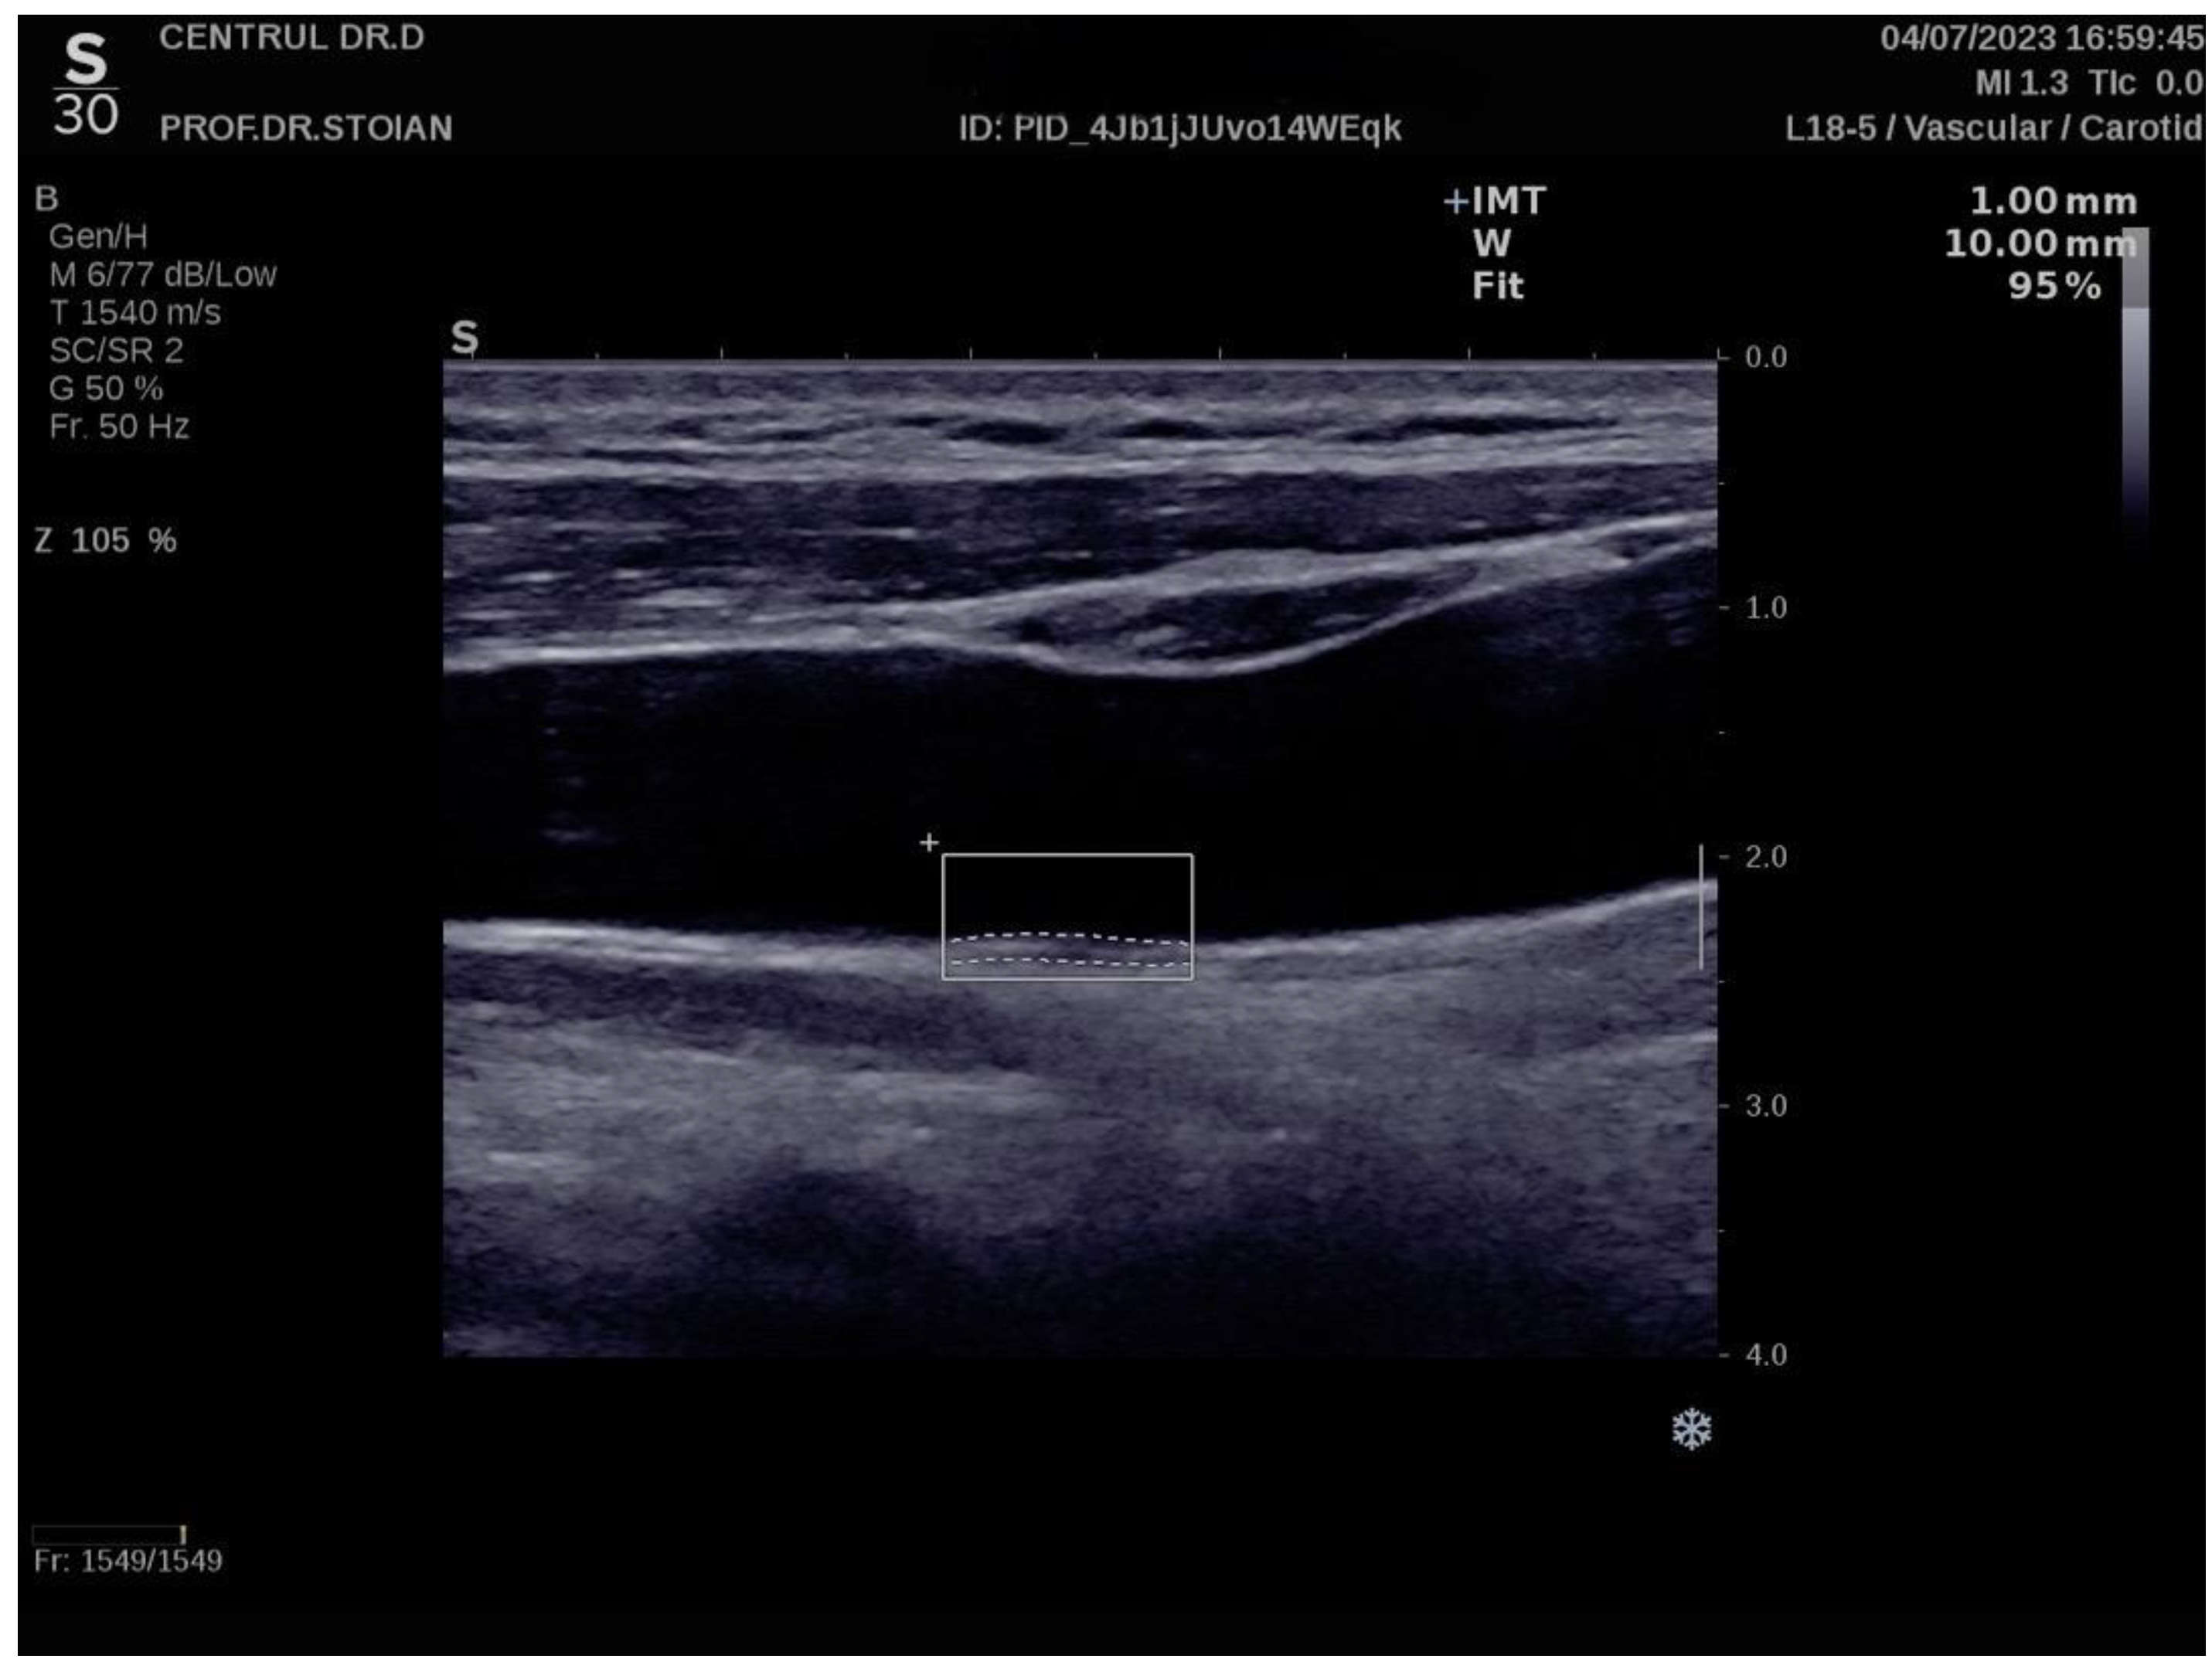

Figure 1 illustrates an example of CIMT evaluation for the left carotid artery obtained using this method in a normoweight subject, whose CIMT value falls within optimal limits. In contrast, Figure 2 depicts an elevated left CIMT value of 1 mm, observed in a patient with grade II obesity. It is important to note that personal data of the evaluated subjects are not displayed to ensure confidentiality.

Figure 2.

Example of a high value of left CIMT measurement in a subject with obesity grade II using the Aixplorer MACH 30 ultrasound system.

The Aixplorer MACH 30 ultrasound system (SuperSonic Imagine, Aix-en-Provence, France) was used to conduct an ultrasonographic assessment of carotid intima-media thickness. A certified and highly experienced sonographer conducted carotid ultrasonography on each participant included in this study. The procedure involved carefully positioning each subject to ensure optimal visualization of the carotid artery and applying a conductive gel to facilitate sound wave transmission. The sonographer then meticulously scanned the carotid arteries, using appropriate transducer settings based on individual anatomical characteristics, such as neck structure and adipose tissue distribution: SL 18-5 (5–18 MHz) or SL 10-2 (2–10 MHz). The CIMT values were automatically computed by the advanced software embedded within the ultrasound system (SuperSonic Imagine 3.0, Aix-en-Provence, France). This software analyzes the ultrasound images in real-time, providing precise measurements of the intima-media thickness without requiring manual calculation, ensuring both accuracy and efficiency in the evaluation process. The ultrasound images were captured during the end-diastolic phase, identified by the occurrence of the R wave on the electrocardiogram, ensuring consistency in arterial relaxation and minimizing variability in measurements [66]. For each participant, six separate CIMT measurements were taken, with three measurements performed on both the left and right carotid arteries. The measurements were carefully averaged to produce a mean CIMT value, which was subsequently used for analysis in this study. This approach helped to enhance the precision and reliability of the data by accounting for natural variations in arterial thickness across different locations and ensuring that the final CIMT value represented an accurate reflection of each patient’s vascular status. To obtain optimal visualization of the right and left common carotid arteries, the subject is positioned in a supine position and instructed to extend their neck backward as far as comfortably possible, enhancing exposure of the cervical region. Additionally, the examiner carefully chooses the most suitable ultrasound transducer, ensuring that the correct frequency range is used to maximize image clarity and resolution for accurate assessment of the CIMT. The scanning procedure begins with a transverse approach, starting at the clavicle and moving upward along the neck to identify the carotid bulb and the bifurcation of the common carotid artery into the internal and external carotid arteries. Once the carotid bulb is located, the examiner transitions to longitudinal scanning, allowing for a detailed assessment of the arterial walls and a more precise measurement of the CIMT along the length of the artery. This systematic approach ensures thorough visualization of both the structure and flow characteristics within the carotid arteries. In this section, the carotid bulb is visualized on the left side of the ultrasound screen. Measurements are taken from the posterior wall of the carotid artery, specifically 1 to 2 cm distal to the carotid bulb. This location is chosen to avoid the geometrical irregularities of the bulb itself and to obtain accurate and consistent CIMT values from a more uniform segment of the arterial wall [67]. At end-diastole, the image is frozen, and the software automatically measures the CIMT in the examiner’s selected region of interest, ensuring consistency and precision [68,69].